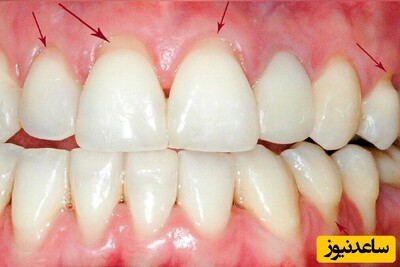

لثه سالم صورتی رنگ، محکم، نازک و دارای کنگره هایی هماهنگ با لبه دندانها و سطح لثه حالت پوست پرتغالی و دان دان است لثه ها از بافت های نرم به وجود آمده اند. آن ها بخش انتهایی دندان ها (ریشه دندان) را احاطه کرده اند. مراقبت از لثه به اندازه مراقبت از دندان ها دارای اهمیت می باشد. بیماری لثه، نوعی عفونت است و عامل ایجاد کننده آن پلاک میکروبی بوده که همان لایه چسبناکی است که بر روی دندان ها و لثه انباشته می شود.

لثه های قرمز، پف کرده یا نازک می توانند نشانه ورم لثه باشند. جهت جلوگیری از پیشرفت التهاب لثه حائز اهمیت است که آن را درمان کنید. شکل جدی تر بیماری لثه باعث می شود لثه ها از دندان عقب نشینی کنند و شکل کیسه ای را پیدا کند که آلوده شده است.

نوار چسبنده ای که روی دندان تشکیل می شود جرم نامیده می شود (ممکن است متوجه یک ماده سفید یا زرد رنگ در بین دندان ها یا در طول خط دندان شوید) این جرم می تواند پیشروی کرده و تارتار شود(سخت، رسوبات کلسیمی که باید توسط دندانپزشک برطرف شوند) که با مسواک زدن یا نخ دندان کشیدن منظم برطرف نمی شود.